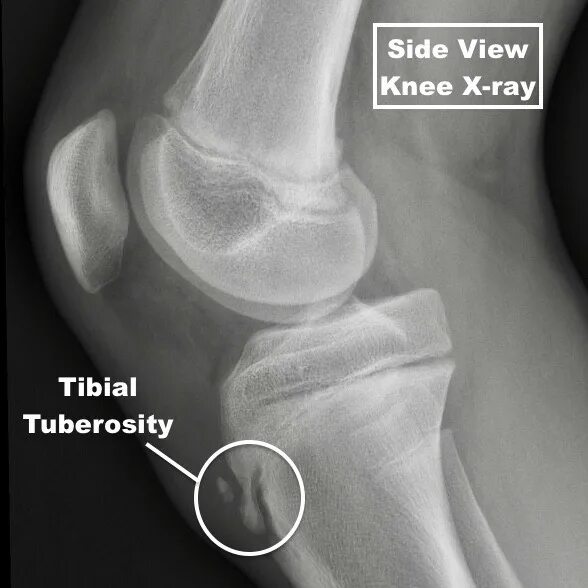

Болезнь шляттера код по мкб